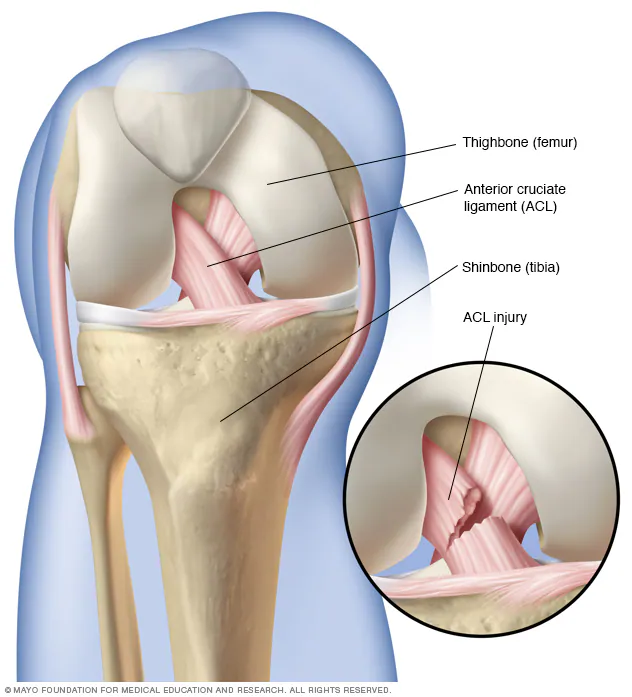

- Previous knee injury (fractures, ligament injuries, meniscus tears)

- MRI scans – used selectively to assess cartilage, meniscus, or ligaments